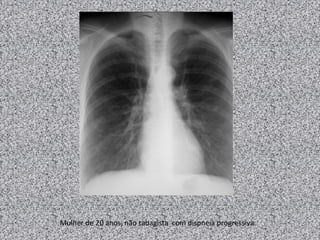

Bronquite crônica

Mulher de 20 anos, não tabagista com dispneia progressiva.

Linfangioleiomiomatose: mulher de 20 anos não tabagista.